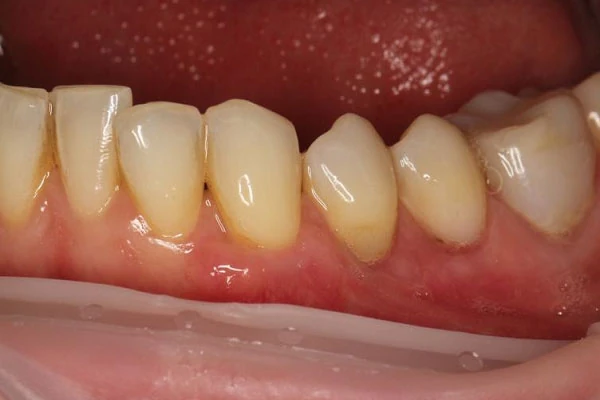

- рецессии (оголение корня зуба)

- клиновидный дефект